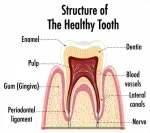

На консультации врач стучала мне прибором по зубам 7-му и 8-му, дула воздухом, прыскала холодной водой - ни на один раздражитель зубы не реагировали болью, о чем я ей и сказала. Тогда мне велели сделать снимок зуба мудрости 8-го. По снимку врач определила, что воспалился нерв, от этого и стук в ухе и что после удаления нерва все прекратится. Я согласилась на лечение. Рассверлив зуб, врач сказала, что зуб здоров, вероятно, все-таки причина в 7 зубе. По действиям врача я поняла, что она чистит канал и удаляет нерв в 7-ом. На вопрос: "Зачем?!", она ответила: "Ну он же у вас болит". Я ответила, что не болит и не болел. Врач пожала плечами, мол, она, наверно, меня не поняла. В итоге я заплатила как за пульпит 7-го зуба. 8 зуб остался пока с временной пломбой.

На снимке 8-ой зуб и половинка 7-го. Подозреваю, что и 8-ой и 7-ой зуб были здоровым, хоть 7-ой и с пломбой, ну точно не пульпит как она меня уверяла. Подозреваю, что меня просто обманули.

Были ли основания по этому снимку ставить диагноз воспаление нерва или хотя бы кариес?

Насколько позволяет качество снимка, зубы здоровы.